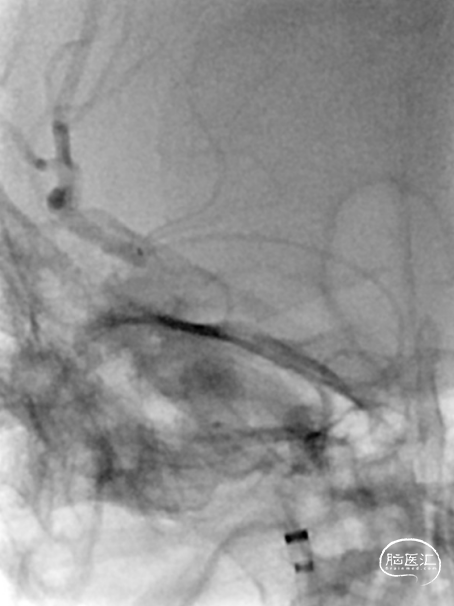

将Synchro(0.014×300cm)微导丝外衬Gateway(2.0×15mm)球囊缓慢通过RMCA M1段狭窄处,球囊定位于RMCA狭窄处缓慢扩张,压力6atm。采用交换技术置入灌注微导管,并将4.0×16mm支架定位于狭窄处释放。

复查造影见支架展开良好,支架内及远端血流通畅,TICI分级3级。术顺,术毕,Proglide缝合术口。

术后第一天复查颅脑CT未见异常染色及大面低密度病灶。

查头颅MRI:右侧基底节区、右侧顶颞岛叶急性脑梗死。